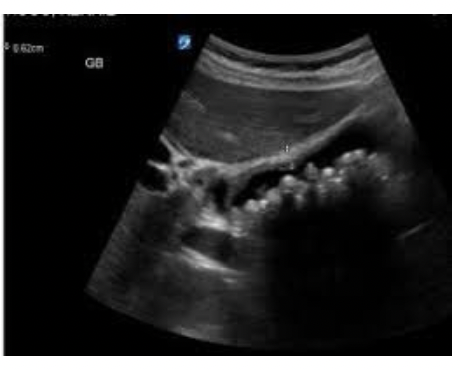

What pathology is in the image below ?

Acute Choleycystitis - Thickened gallbladder wall >3 mm, irregular outline of thickened wall, sonolucent